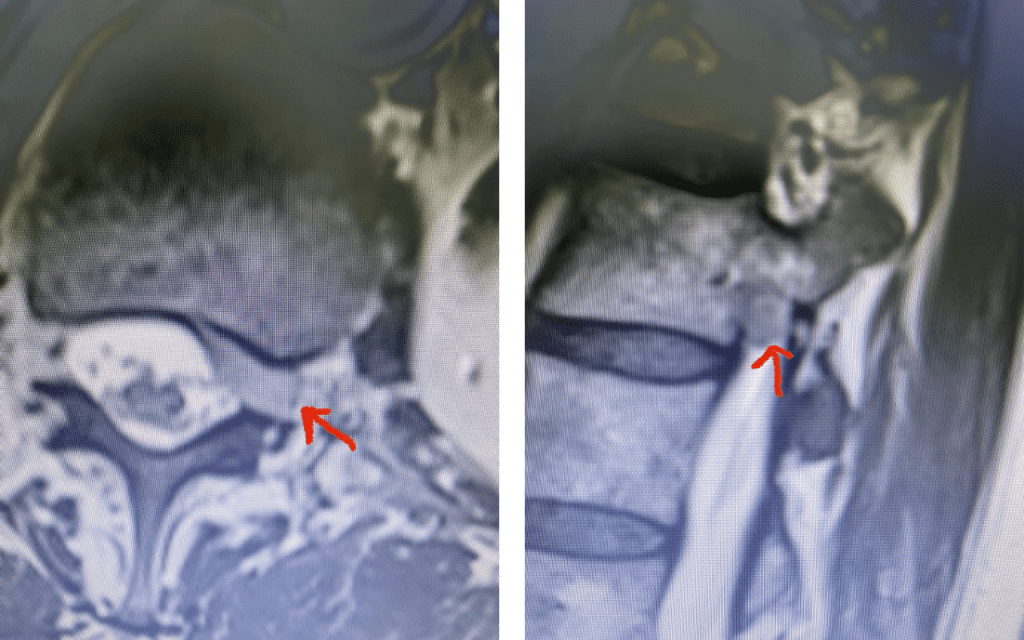

Fig 4: Axial and Sagittal T2-weighted lumbar MRI demonstrating a left lateral foraminal disc herniation (red arrow) causing compression of the exiting L1 nerve root against the undersurface of the pedicle of L1.